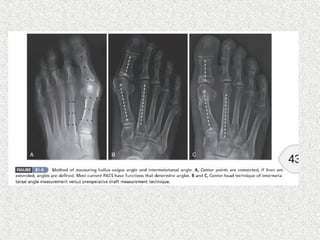

HALLUX VALGUS ANGLE

Normal <15

Mild <20

Moderate 20-40

Severe >40

1st

/2nd

Inter Metatarsal Angle (IMA)

Normal <9

Mild <11

Moderate 11-16

Severe >16

CLASSIFICATION NORMAL MILD MODERATE SEVERE

HALLUX VALGUS ANGLE < 15* < 20° 20° to 40° > 40°

1-2 INTERMETATARSAL

ANGLE

< 9* 11° or less. 12 - 15° 16° or more

SUBLUXATION OF THE

LATERAL

SESAMOID, AS MEASURED

ON AN AP RADIOGRAPH

Nil or

minimal

< 50% 50% to 75% > 75%

Classification